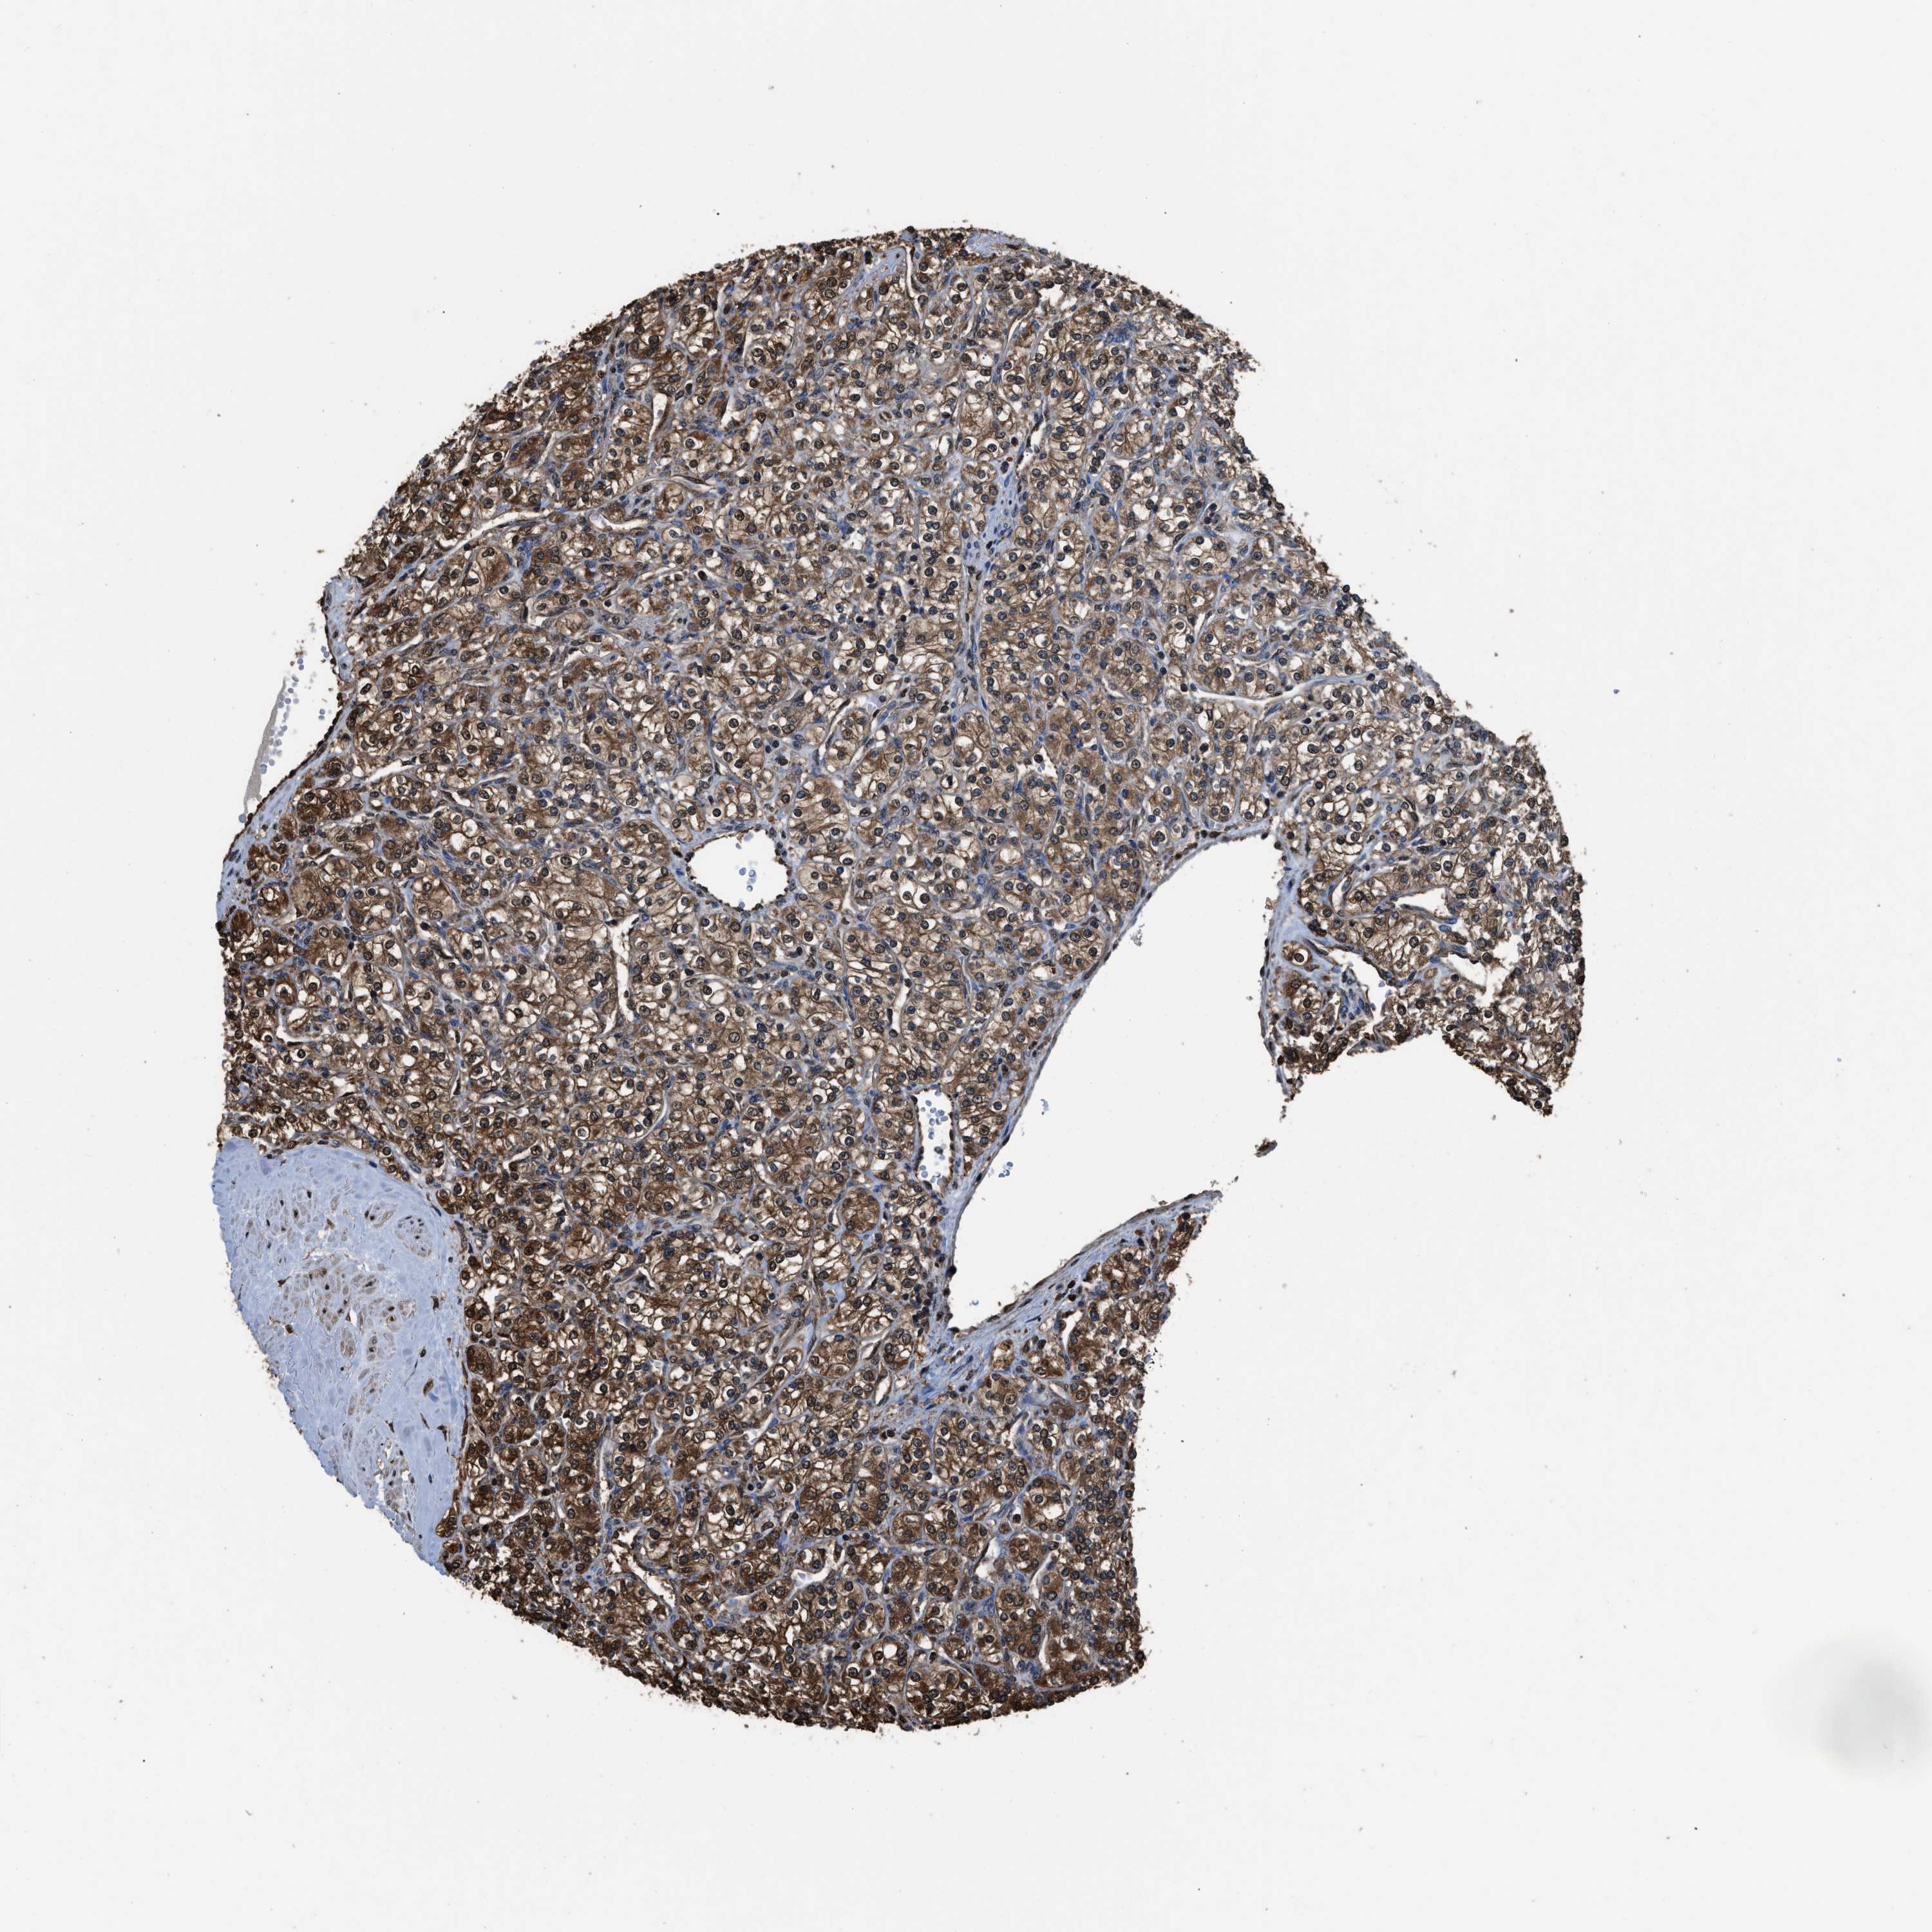

KIDNEY RENAL CLEAR CELL CARCINOMA (TCGA) - Interactive survival scatter ploti

The Survival Scatter plot shows the clinical status (i.e. dead or alive) for all individuals in the patient cohort, based on the same data that underlies the corresponding Kaplan-Meier plots. Patients that are alive at last time for follow-up are shown in blue and patients who have died during the study are shown in red.

The x-axis shows the expression levels (FPKM) of the investigated gene in the tumor tissue at the time of diagnosis. The y-axis shows the follow-up time after diagnosis (years). Both axes are complimented with kernel density curves demonstrating the data density over the axes. The top density plot shows the expression levels (FPKM) distribution among dead (red) and alive patients (blue). The right density plot shows the data density of the survived years of dead patients with high and low expression levels respectively, stratified using the cutoff indicated by the vertical dashed line through the Survival Scatter plot. This cutoff is automatically defined based on the FPKM cutoff that minimizes the p-score. The cutoff can be changed by dragging the vertical line or by entering a cutoff value in the square labeled "Current cut-off".

Under the Survival Scatter plot the p-score landscape (black curve; left axis) is shown together with dead median separation (red curve; right axis). Dead median separation is the difference in median mRNA expression between patients who have died with high and low expression, respectively. It is calculated as follows: median FPKM expression of dead patients with high expression - median FPKM expression of dead patients with low expression. This is intended to aid the user in visually exploring custom cutoffs and the associated p-scores and dead median separation.

Individual patient data is displayed and can be filtered by clicking on one or more of the category buttons on the top of the page. Categories describing expression level and patient information include: high, low, alive, dead, female, male and tumor stages. The scale of the x-axis can be toggled between linear and log-scale by clicking on the "x log" button. Mouse-over function shows TCGA ID, patient information and mRNA expression (FPKM) for each patient.

& Survival analysisi

Kaplan-Meier plots summarize results from analysis of correlation between mRNA expression level and patient survival. Patients were divided based on level of expression into one of the two groups "low" (under cut off) or "high" (over cut off). X-axis shows time for survival (years) and y-axis shows the probability of survival, where 1.0 corresponds to 100 percent.

FNTA is not prognostic in Kidney Renal Clear Cell Carcinoma (TCGA)

Best expression cut offi

Based on the FPKM value of each gene, patients were classified into two groups and association between prognosis (survival) and gene expression (FPKM) was examined. The best expression cut-off refers the FPKM value that yields maximal difference with regard to survival between the two groups at the lowest log-rank P-value. Best expression cut-off was selected based on survival analysis .

When clicking on this number, the vertical dashed line indicating cut-off, the interactive survival plot, and the Kaplan-Meier curve will be adjusted to show results based on the best expression cut-off.

: 32.07

TCGA RNA samplesi

RNA-seq data is reported as average FPKM (number Fragments Per Kilobase of exon per Million reads), generated by the The Cancer Genome Atlas (TCGA) .

Normal distribution across the dataset is visualized with box plots, shown as median and 25th and 75th percentiles. Points are displayed as outliers if they are above or below 1.5 times the interquartile range. FPKM values of the individual samples are presented next to the box plot.

Average pTPM 37.7

Number of samples 521